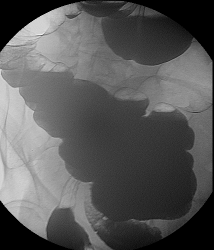

Это исследование я проводил сегодня утром, помимо данного участка с "органикой" есть ещё один участок, который отчётливо видно на МСКТ при анализе изображений, но почему то мой более старший коллега ни стал об этом указывать ссылаясь на то, что преригатива скопического и эндоскопического исследований, у нас там конечно ни шуточная баталия разгорелась, и вообще поставил данный участой симметричного сужения подвопросом:

Именно этим мне и показался данный случай интересным, получается именно данный участок видели эндоскописты, а это участок поперечного отдела ободочной кишки, даже почти селезёночный угол, чётко видно на МСКТ. И получается что первично-множественный рак толстого кишечника, если я не прав поправте меня.

Множественный дивертикулёз сигмовидного, нисходящего и поперечного отделов ободочной кишки.

То что в нисходящем отделе ободочной кишки-дивертикулез это на 100%, по поводу "сигмы" ещё можно посомниваться, но этот участок попадает под резекцию, у морфологов узнаю, а вот ампула прямой кишки, это да, что как то я сомневаюсь до сих пор что это остаточные каловые массы, пациент подготовлен-отлично, возможно полип, но как бы ещё хуже не оказалось, но в дальнейшем всё равно попадёт к нам на контроль, плюс эндоскописты. Кстати вроде планы ещё резко сменились по ведению этого пациента, думаю хирурги озадачились, хотя трансфузиолог свои запеси уже оставил.

Описание операции: ЭТН. Срединная лапаротомия. При ревизии в селезеночном углу толстой кишки циркулярная опухоль до 10 см диаметром, в проксимальной трети сигмовидной кишки блюдцеобразная опухоль до 5 см диаметром, заниающая 1/2 окружности кишки, долихосигма. В печени, забрюшинном пространстве, желудке, тонкой кишке патологии не выявлено, желчный пузырь ранее оперативно удален. Мобилизована сигмовидная, нисходящая, поперечноободочная кишка до правой ветви средней толстокишечной аретрии, выполнена левосторонняя гемиколэктомия. Сформирован трансвенрзо-сигмоанастомоз 2-рядным узловым швом. Дефект брыжейки ушит. Гемостаз. Счет салфеток. Трубчатый дренаж в левый боковой канал. Послойные швы на рану.

Описание препарата Удаленная левая половина толстой кишки длиной до 1,2 м с опухолью до 10 см диаметром, циркулярно суживающей просвет и опухолью до 5 см диаметром, блюдцеобразной занимающей 1\2 окружности кишки. В среденй трети сигмовидной кишки дивертикул до 1 см диамером.